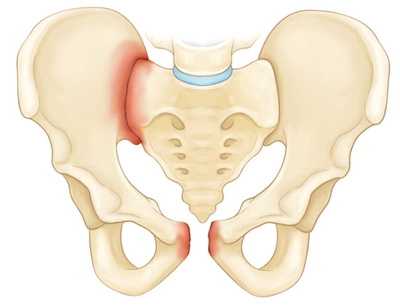

Стабильные переломы. Данный тип переломов обычно отличается наличием лишь одной линии перелома и сохранением анатомии тазового кольца. Низкоэнергетические переломы - это обычно стабильные повреждения. К стабильным переломам относятся следующие:

Перелом крыла подвздошной кости.

- Стабильные (переломы костей таза, не сопровождающиеся нарушением целостности тазового кольца). В эту группу входят изолированные и краевые переломы костей таза.

- Краевые повреждения костей, не участвующих в образовании тазового кольца.

- Повреждения костей, образующих тазовое кольцо, без потери его непрерывности.